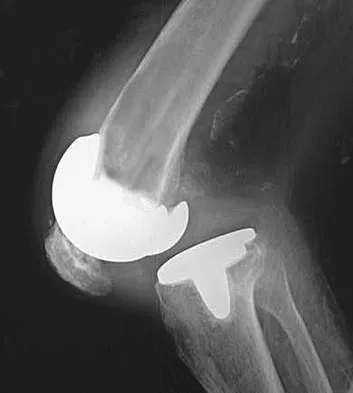

High-yield MCQs for Set 1 on Hip & Knee Reconstruction, perfect for AAOS & ABOS board review. Covers arthropl…